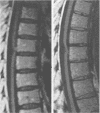

Two cases of anterior spinal hernia are presented. The medical literature is reviewed, the syndrome characterised, and its cause and treatment discussed. The patient is typically middle aged with a history of stepwise slowly progressive mid-thoracic anterior hemicord syndrome manifesting as hemianalgesia below the affected segment, followed by contralateral lower limb spasticity that develops into an asymmetric paraparesis with sparing of dorsal column sensation. Radiological investigation demonstrates an enlarged dorsal arachnoid space in association with an apparently focally narrowed thoracic cord, kinked towards the anterior dura. At operation the cord is found to be prolapsed into an anterolateral dural diverticulum. The most likely cause of this syndrome is anterior spinal artery segmental branch ischaemia, in a cord chronically incarcerated in a congenital anterior meningocele. This readily treatable condition should be considered in all cases of thoracic cord dysfunction and surgical repair effected early to prevent stepwise progression to paraplegia.